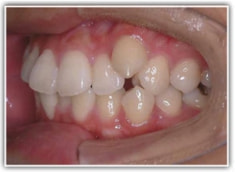

治療前

左右の顎顔面の非対称と、歯の位置の非対称を伴うケースです。

上下顎とも前突しており、叢生もあります。分析値からも抜歯対象症例です。

左右の非対称が骨格的にも、歯槽的にも存在し、特に顎の中での上下の歯の位置に、下顎前歯一本分の左右のズレが認められるので、かなり強い非対称といえます。